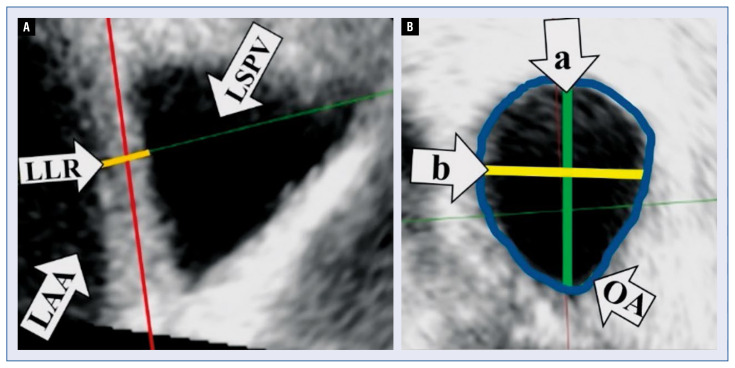

Background: A direct comparison of three-dimensional transesophageal echocardiography (3DTEE) and cardiac computed tomography imaging has demonstrated good inter-technique agreement for the following pulmonary vein (PV) parameters: the ostium area of the right superior PV (RSPV) and its major (a) and minor axis (b) diameters, the left lateral ridge and the minor axis (b) diameter of the left superior PV. Herein, under investigation, was the predictive value of these parameters for arrhythmia recurrence (AR) after PV isolation with the 28 mm second generation cryoballoon (CBG2).

背景:三维经食管超声心动图(3DTEE)和心脏计算机断层扫描成像的直接比较表明,以下肺静脉(PV)参数在技术间具有良好的一致性:右上肺静脉(RSPV)的口面积及其长轴(A)和短轴(b)直径,左侧脊和左上PV的短轴(b)直径。在此,我们正在研究这些参数对28mm第二代冷冻气球(CBG2)PV隔离后心律失常复发(AR)的预测价值。方法:对111例(67名男性,平均年龄58.06±10.58岁)在CBG2 PV隔离前接受3DTEE的阵发性心房颤动患者进行随访。在AR的情况下提供了“逐点”重做干预,并定义了重新连接的PV。结果:在617±258.86天的平均随访中,65名(58.9%)患者没有AR。发现较长的RSPV b是AR的唯一显著预测因素(危险比[HR]1.059;95%置信区间[CI]1.00-1.121;p=0.048)。RSPV b≥28 mm导致AR风险增加三倍(HR3.010;95%CI1.270-7.134,p=0.012)。RSPV b与AR的相关性与冷冻应用的生物物理参数无关。在25名“重做”患者中,发现RSPV中重新连接的发生率是其他3个PV的1.75倍。结论:3DTEE测量右上肺静脉b可能是CBG2分离肺静脉后AR的重要预测指标。如果RSPV b超过28 mm,可能会考虑采用替代PV隔离技术或使用更大的气球。